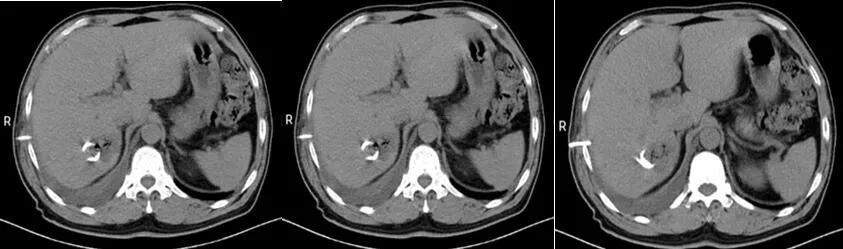

胸腔闭式引流术后(图四)